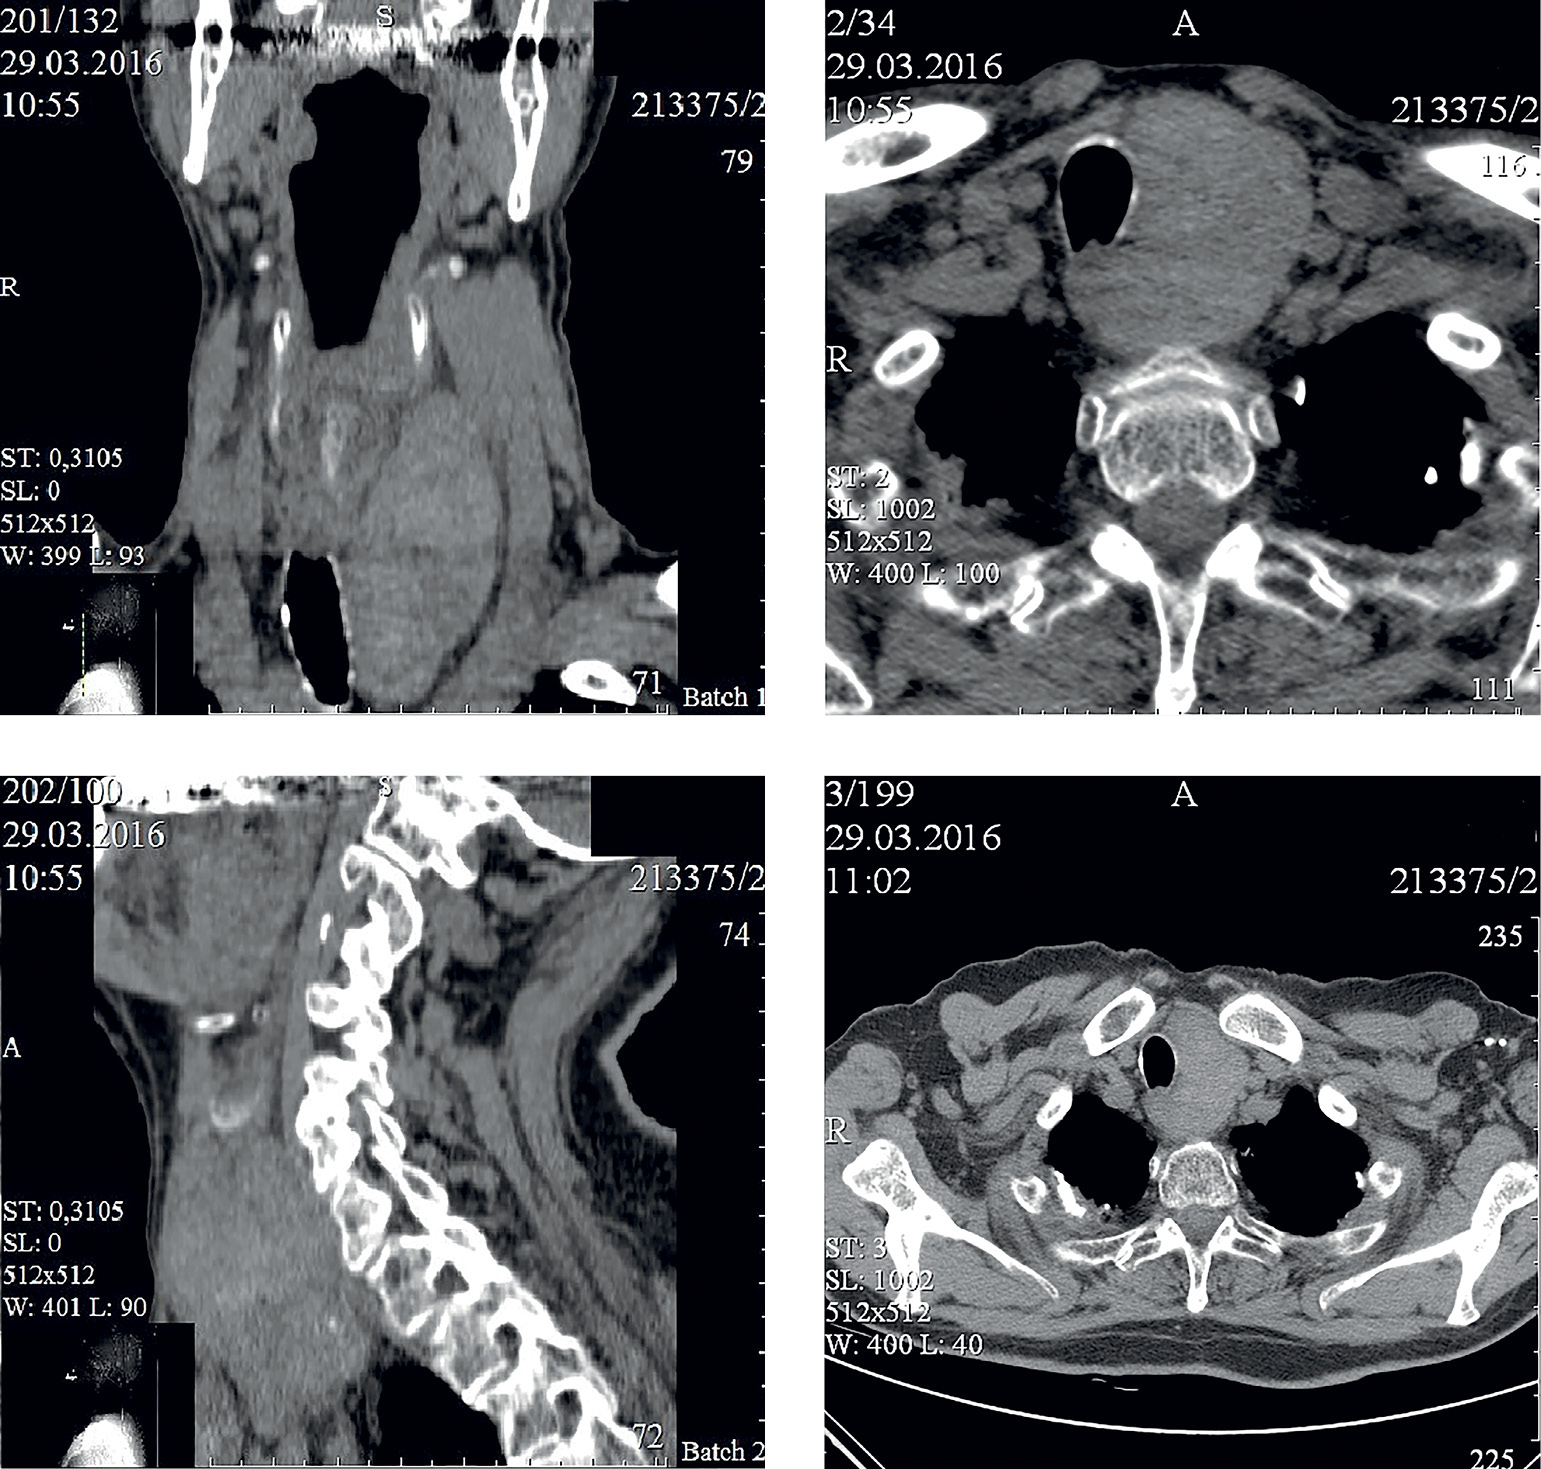

2. Рисунок 4. Компьютерная томография органов шеи, 2016 г.

Тема

Тип Исследовательские инструменты